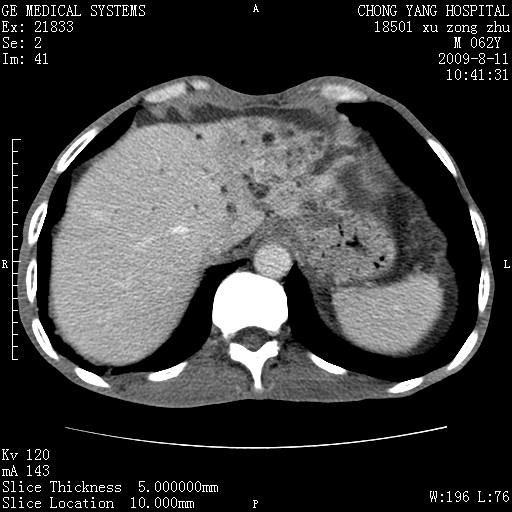

以下是引用杀毒软件在2009-8-11 16:35:00的发言:[br]肝内胆管扩张局限于左叶,胆管内有结石伴肝外胆管结石,胆管壁增厚呈弥漫性并发腹腔积液,胰腺边界模糊。[br][br]考虑---胆总管及肝内胆管结石继发胆管炎及胰腺炎,左肾下极囊肿,腹水。

以下是引用zjzjr在2009-8-11 17:35:00的发言:[br]肝内胆管扩张局限于左叶,胆管内有结石伴肝外胆管结石,胆管壁增厚呈弥漫性并发腹腔积液。[br][br]考虑---胆总管及肝内胆管结石继发胆管炎,左肾下极囊肿,腹水。